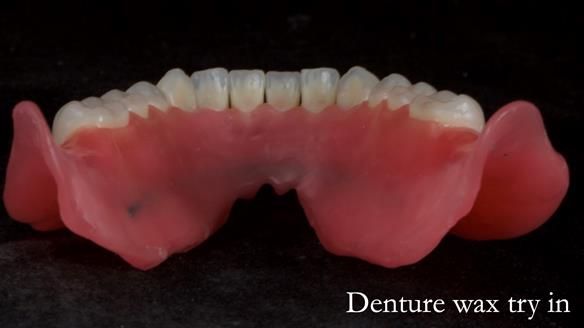

In this edition, I present the complete denture treatment for Kate, a 69-year-old American woman living in Garstang, UK. Kate had been edentulous for many years and required a set of complete dentures that closely mimicked her natural teeth. The new upper and lower dentures provided excellent retention and stability, with significant suction in the upper denture. Below, I detail the step-by-step process of her treatment, as well as my workflow for implant-supported overdentures for patients who may require them.

Treatment Process: I provided the clinical work while Rowan Garstang and Sam Hesketh delivered the technical aspects. The treatment required fifteen visits to fit and review Edgar.